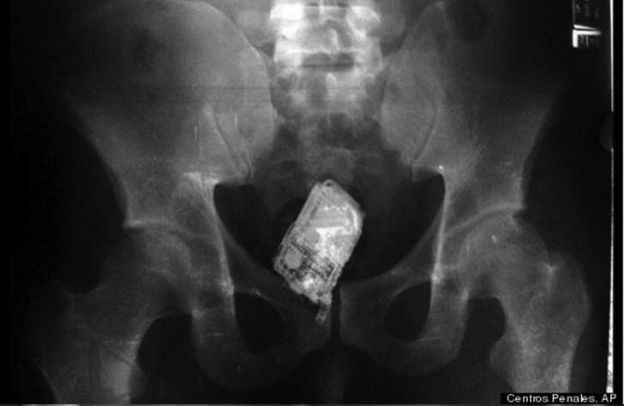

Telefone Celular